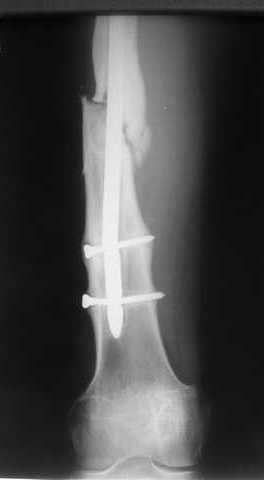

Пациенту М., 30-ти лет, 1,5 года назад в одной из московских больниц был выполнен остеосинтез бедренной кости штифтом UFN (диаметр штифта 9 мм).

К нам больной поступил с признаками ложного сустава бедренной кости, перелома

штифта и дистального блокирующего винта (images 1,2,3).

27 марта выполнено удаление блокирующих винтов (сломанный винт пришлось высверливать цапфен-бором), сломанного штифта (дистальный фрагмент удален через канал, образованный разверткой из коленного сустава - image 4),

рассверливание костно-мозгового канала, реостеосинтез штифтом UFN (при проведении штифта в дистальном отломке мы использовали поляризующий винт, диаметр штифта 10 мм). После операции в связи гемартрозом дважды (на 1 и 3 сутки) выполняли пункцию коленного сустава. Сейчас признаков скопления жидкости в полости сустава нет. Послеоперационные рентгенограммы - images 5, 6, 7.